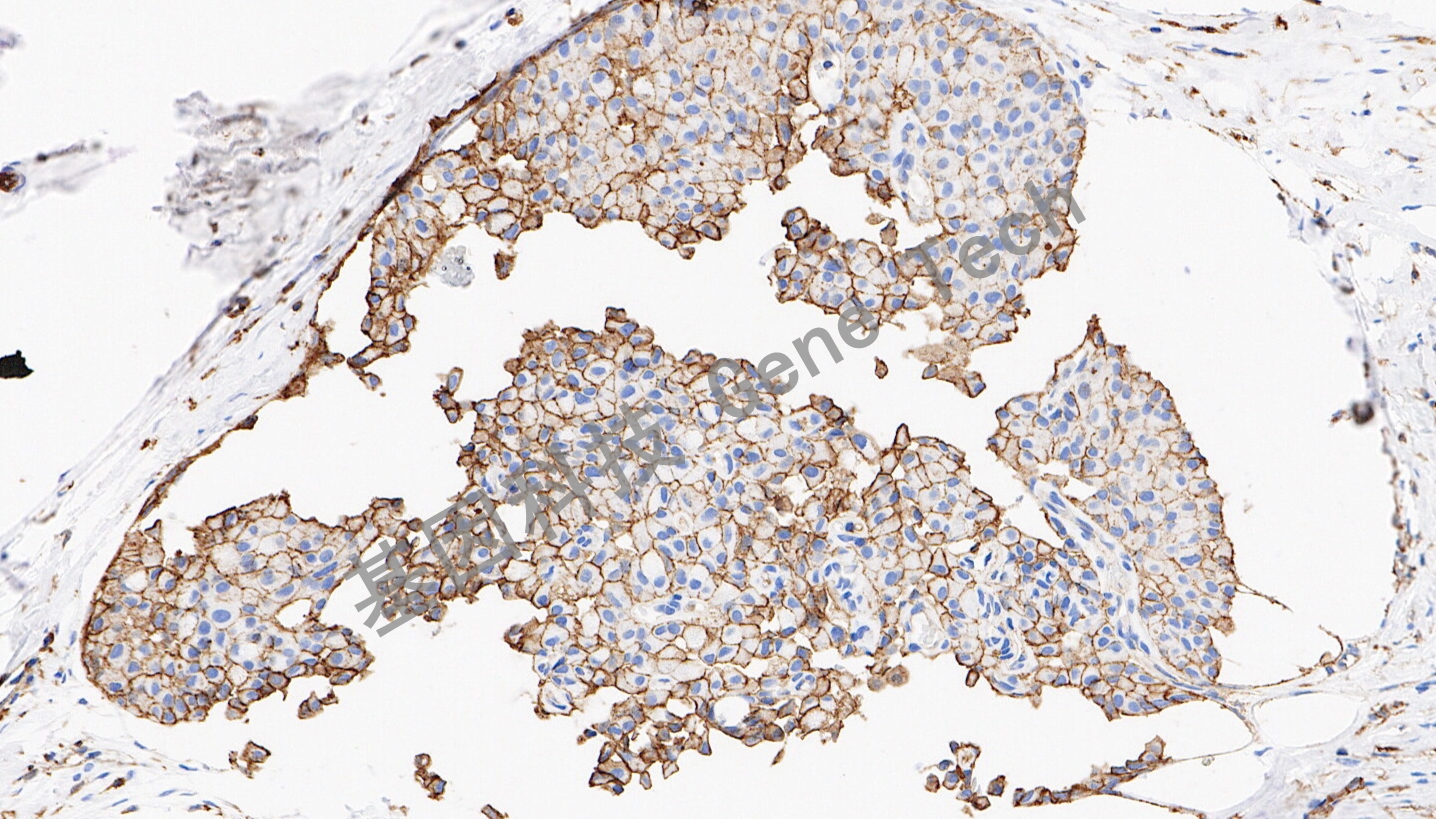

| 乳腺癌石蠟切片,用 JAM-A (GT2598)染色,細(xì)胞膜陽(yáng)性,DAB 顯色。 | ||

| 預(yù)處理:高pH熱修復(fù) | 陽(yáng)性部位:細(xì)胞膜 | 陽(yáng)性對(duì)照:乳腺癌 |

| 簡(jiǎn)介:連接粘附分子A(JAM-A)也被稱(chēng)為JAM-1,是位于上皮細(xì)胞和內(nèi)皮細(xì)胞間緊密連接處的一種跨膜糖蛋白,屬于免疫球蛋白超家族。JAM-A調(diào)節(jié)多種細(xì)胞過(guò)程,包括緊密連接組裝、上皮-間充質(zhì)轉(zhuǎn)化(EMT)、白細(xì)胞遷移、病毒結(jié)合、血小板活化和血管生成。JAM-A通過(guò)緊密連接的啟動(dòng)引起同型細(xì)胞間的黏附,與腫瘤黏附、浸潤(rùn)和轉(zhuǎn)移密切相關(guān)。研究表明,JAM-A在乳腺癌患者腫瘤標(biāo)本呈異常高表達(dá),并提示預(yù)后不良。 | ||